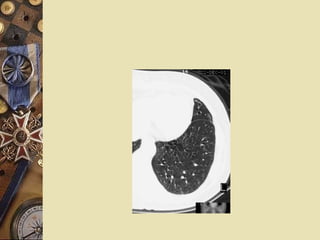

Evaluation CT or HRCT:   high sensitivity and specificity Diamond ring sign:  dilated bronchi appear as ring structures with internal diameters greater than those of their accompany pulmonary artery branches.

Evaluation CT orHRCT: high sensitivity and specificity Diamond ring sign: dilated bronchi appear as ring structures with internal diameters greater than those of their accompany pulmonary artery branches.